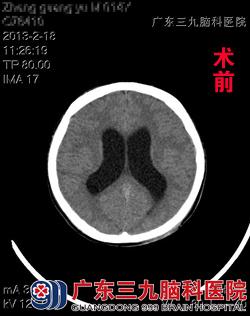

14岁的小郑不幸遭遇车祸致头部受伤,当即不省人事,被120急送当地医院救治,头部CT检查示左侧小脑半球挫裂伤并出血;急诊行“脑外伤行硬膜外及硬膜下血肿清除+后颅窝减压术”、 “右侧脑室外引流术”,术后3周康复出院。不料出院后1月余,小郑开始感到头痛头晕,并伴有行走不稳症状,症状持续3天后在当地医院复诊行CT检查示:脑积水。经朋友介绍而来广东三九脑科医院神经外七科求进一步治疗。 www.999brain.com

入院后完善相关检查,明确脑脊液性状,确定手术适应症后,小郑在全麻下接受了脑室腹腔分流术,术程顺利,术后予以抗炎、止血、营养支持、暂禁食水等处理。术后10天康复出院。www.999brain.com